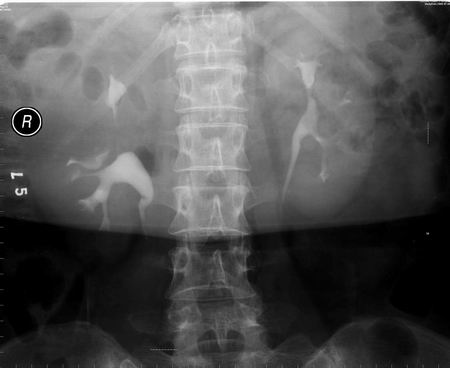

以下是引用向医生在2005-2-3 16:50:59的发言:[br]右侧肾盂上部及上肾盏受压,压迹呈弧形,边缘光滑,肾盏无侵蚀现象,局部肾轮廓似有增大。[br]意见:右肾上极占位。

以下是引用lkc8963在2005-2-9 20:43:32的发言:[br]支持右上极良性占位性病变.右肾区无钙化,局部无明显突出,肾盏受压变形,受压肾盏间似见片状造影剂充盈,功能正常,可能为囊肿或肾盏憩室,因为病变与收集系统相通.